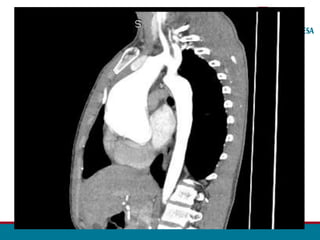

ANGIOTOMOGRAFIA DA AORTA TOTAL – 28/05:

• Presença de volumosa dilatação aneurismática do segmento tubular

ascendente aórtico, com o diâmetro de até 74 mm, sem trombo.

• Nota-se a redução moderada do diâmetro luminal aórtico do arco, sendo

mais intenso na região do istmo (diâmetro mínimo luminal efetivo no istmo é

de aproximadamente 6,5 mm), havendo dilatação fusiforme pós-

estenótica no terço proximal descendente aórtico com até 36 mm.

• O segmento mais distal descendente da aorta apresenta o diâmetro normal.

• São evidenciadas diversas artérias dilatadas moderadamente

intercostais da metade superior, bilaterais, notando-se ainda leve /

moderada dilatação bilateral das artérias torácicas internas.

ANGIO TOMOGRAFIA

• Segmento estenosado

• Circulação colateral

• Planejamento cirúrgico

•Acompanhamento pós - OP